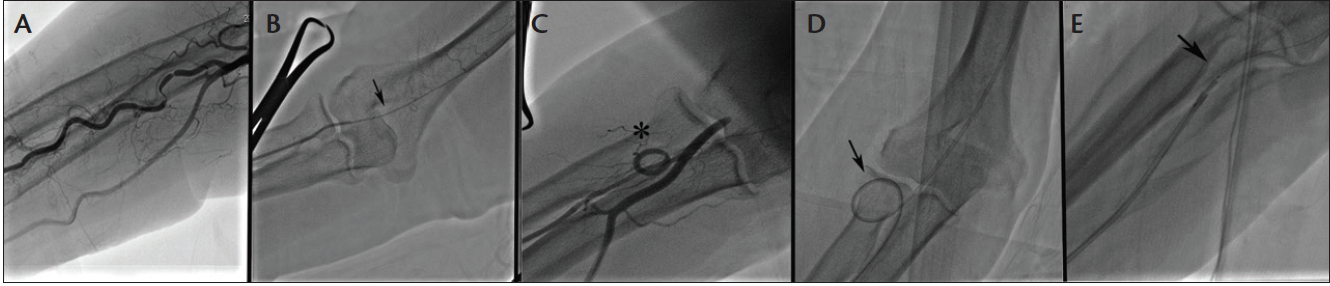

Poor guide catheter support due to acute or anomalous coronary takeoff, tortuous subclavian anatomy, enlarged aorta, or coronary angulation, calcification, and tortuosity are frequent causes of frustration for TR access operators and are often the cause of failure.11 A strong knowledge of techniques and technology available significantly increases TR access success rates.10,11 The difficulty in delivering a long stent in a distal coronary segment is not infrequent with TR access despite successful initial angiography and balloon angioplasty. The poor backup support is due to the subclavian and ascending aorta angulation that limits any applied force to be directed at the guide catheter tip and distal equipment. Therefore, it is more important to adequately predilate lesions with noncompliant balloons or atherectomy, especially in calcific vessels. Use of a larger guide or buddy wire has been suggested to resolve these issues. However, we find the use of a guide extension technique with either the GuideLiner catheter (Vascular Solutions, Inc.) or the Guidezilla (Boston Scientific Corporation) to be the single most useful technique to facilitate equipment delivery in these circumstances. We routinely advance the GuideLiner device just proximal to the target segment before advancing stents. If there is difficulty with GuideLiner placement, it can be tracked and advanced over a balloon inflated in a distal segment. Another technique that can be useful is to use a Wiggle wire (Abbott Vascular) that can anchor the distal small coronary segments, allowing a better rail for equipment delivery (Figure 4). The TR access failure rates are greatly minimized for complex, calcified, and tortuous lesions when employing one or more of the previously mentioned techniques.

Figure 4. Maximizing backup support of the TR approach for complex coronary interventions. A 64-year-old man with previous stenting presented with Canadian Cardiovascular Society grade III angina and chronic occlusion of the right coronary artery (A). A TR approach was used with an Amplatz left (AL1) guide catheter, and a Pilot 200 guidewire (Abbott Vascular) successfully crossed the occluded segment. The Pilot wire was exchanged to a Wiggle wire (arrow) to anchor the guide, and a GuideLiner catheter (asterisk) was used to advance dilating balloons to the target segments (B). The GuideLiner device was brought to the distal segment using the inflated balloon used as an anchor (B) and then left in a deep-seated position to facilitate delivery of multiple, long drug-eluting stents (C) to treat the entire occluded segment with a good angiographic result (D).